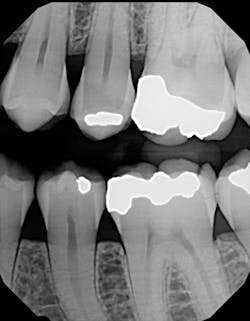

Figure 1: Cracked tooth x-ray

I used it on an elusive cracked tooth case. For once, I could actually see the fracture on an x-ray (figure 1). The noted distal fracture caused a great deal of biting pain for this patient. The one difference I noticed with All-Bond is its application method. Two coats are required and a scrubbing motion is needed during the two-coat process prior to curing. Yes, this is a little more time-consuming, but it did not bother me as much as I thought it might when I initially read the application directions. After I saw the results on the x-ray (figure 2), I knew the thin viscosity did not prohibit any type of condensed end product. The composite material flowed well into the proximal areas, and my patient left with no cracks in No. 19.